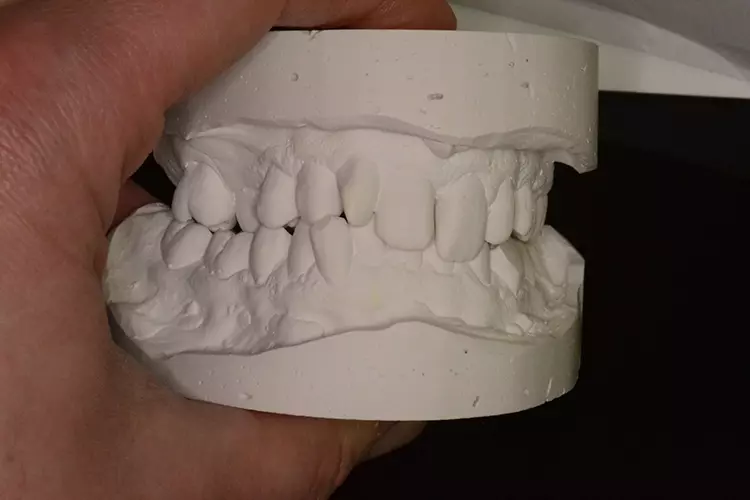

Grundlegend sollten zur Diagnostik und Befunderhebung zunächst Fotos der bestehenden Situation (Fotostatus in Okklusion links und rechts, Aufbiss Ober- und Unterkiefer) angefertigt werden. Außerdem ist anzuraten, ein Situationsmodell zu erstellen.

Auf diesem kann der Zahntechniker entweder durch Dublieren und Aufwachsen oder bei Verwendung eines Intraoralscanners auch digital, sowohl dem Zahnarzt als auch dem Patienten, einen Eindruck der zu erzielenden Situation vermitteln. Selbstverständlich muss auch eine genaue Röntgendiagnostik durchgeführt werden, d. h. mindestens Einzelzahnaufnahmen in Rechtwinkelparalleltechnik bzw. wenn auch operativ implantologisch versorgt werden soll, eine DVT-Diagnostik. In Zusammenhang mit den analogen oder digitalen Situationsmodellen kann mit vorliegendem DVT auch unkompliziert eine Bohrschablone hergestellt werden, um eine mögliche Implantation während der Behandlung navigiert durchführen zu können.

Neugestaltung der Front bei starken Zahnfehlstellungen

Bei dem heute 49-jährigen Patienten wurde seit Kindertagen versäumt, die Ober- und Unterkieferzahnbögen kieferorthopädisch auszurichten. Der Patient leidet seitdem stark unter seinen Zahnfehlstellungen.

Die Fraktur des stark elongierten Zahnes 21 war für den Patienten der Ausgangspunkt, sowohl die Front des Ober- als auch des Unterkiefers prothetisch überarbeiten zu lassen. Dabei wurde der frakturierte Zahn 21 durch ein navigiert eingesetztes Sofortimplantat ersetzt, während die verschachtelt stehenden Zähne 12 und 42 durch eine Brückenversorgung korrigiert wurden (Abb. 4a-j).